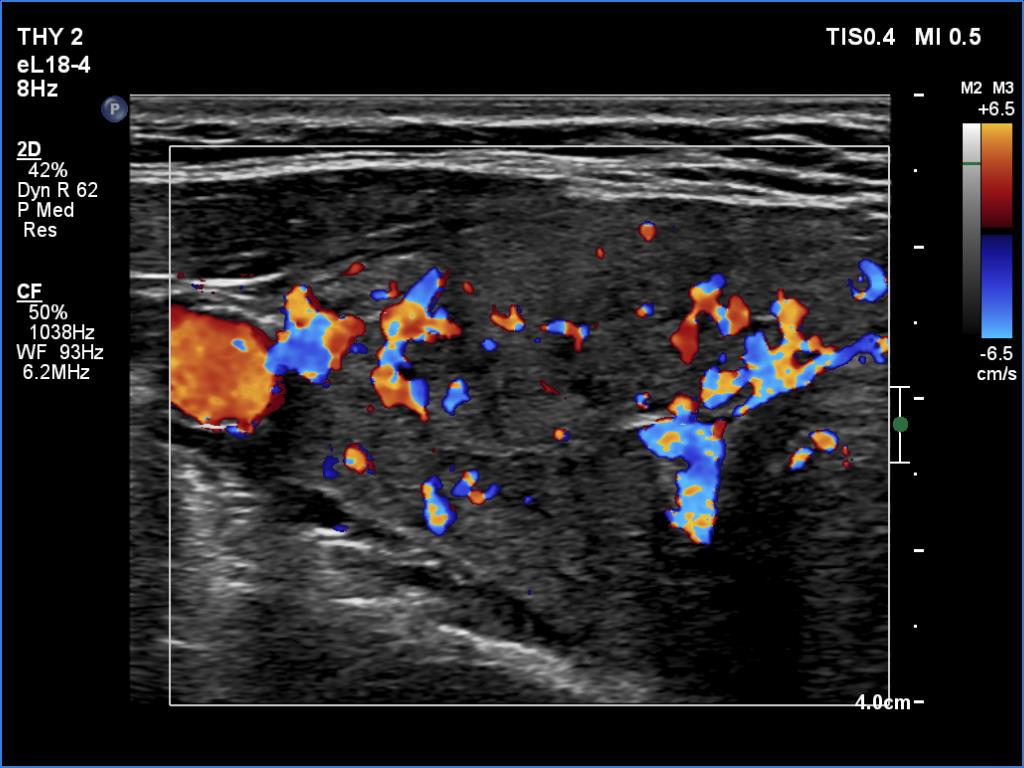

Second examination seven years later (second row of images):

Ultrasonography. The pattern and the thyroid volume were essentially the same as 7 years ago.Suggestion: daily 75 microgram levothyroxine. TSH in 6 months, ultrasound in three years.